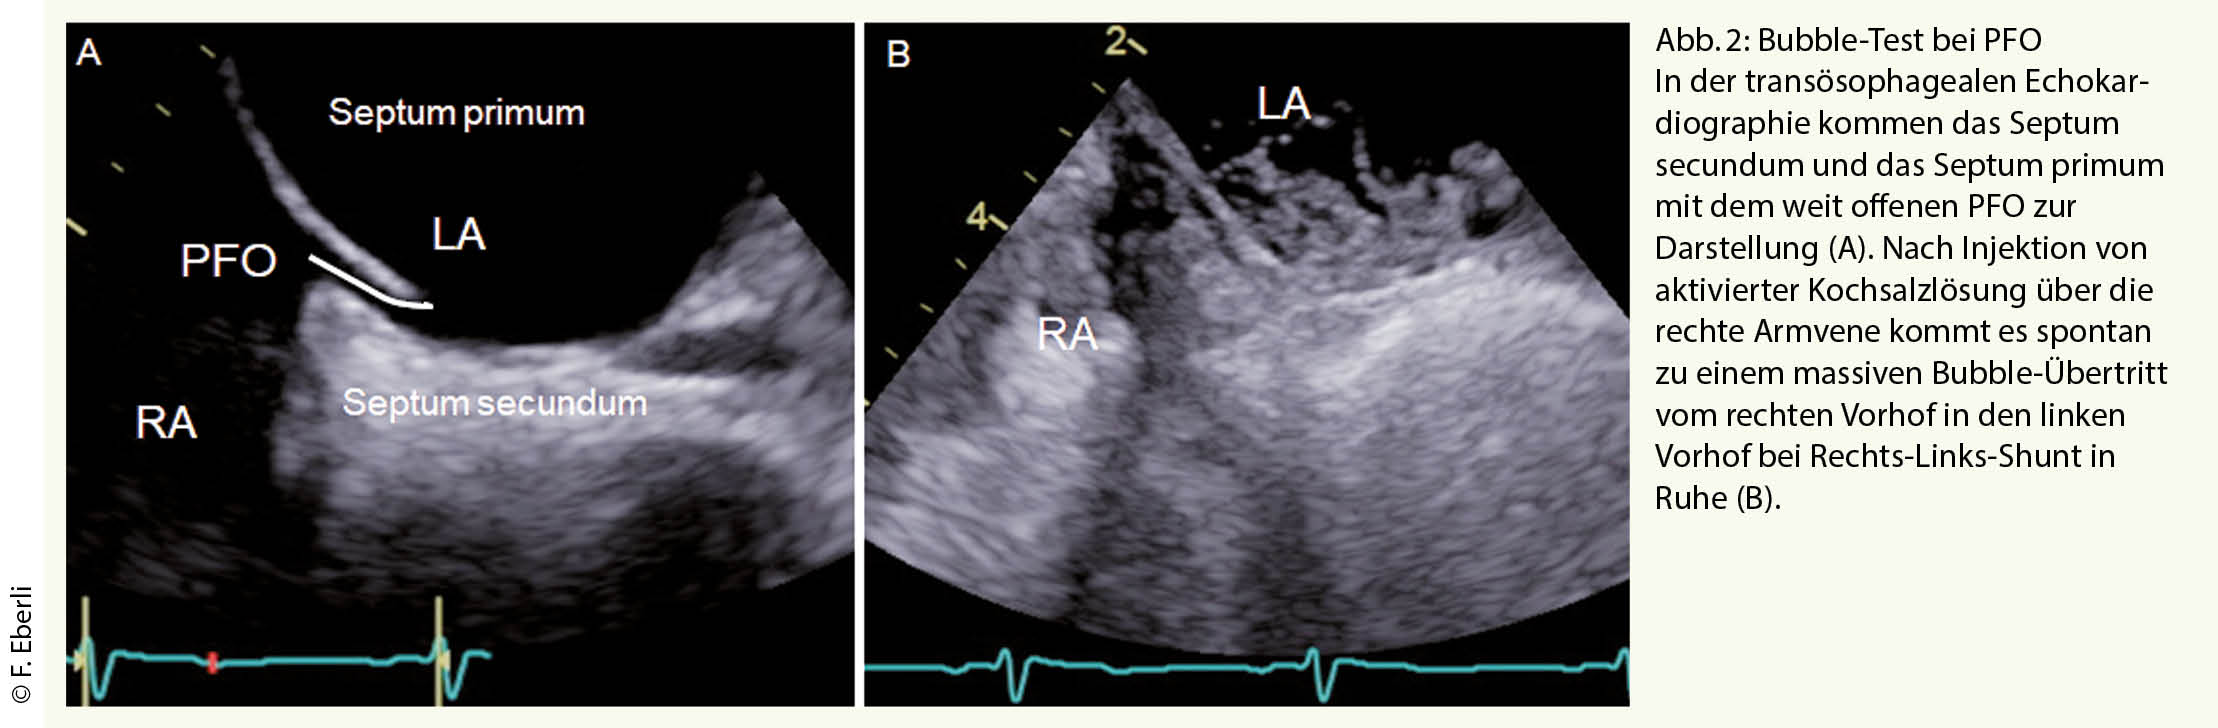

Die transthorakale Echokardiographie dient zum Ausschluss einer kardio-embolischen Quelle. Liegt keine Pathologie am Myokard oder den Klappen vor oder besteht der Verdacht auf eine paradoxe Embolie durch das PFO wird eine transoesophageale Echokardiografie (TEE) angeschlossen. Meist wird bereits bei der transthorakalen Echokardiografie, sicher aber bei der TEE ein Bubble-Test durchgeführt (Abb. 2) um festzustellen, ob ein Rechts-Links-Shunt in Ruhe vorliegt oder mittels eines Valsalva Manövers provoziert werden kann. Die TEE ermöglicht zum einen den Ort des Rechts-Links-Shunts zu eruieren, zum anderen Shuntvitien wie ein Vorhofseptumdefekt, falsch mündende Lungenevenen oder eine pulmonale A-V Malformation auszuschliessen. Mittels TEE wird die Morphologie und Anatomie des PFO und des Vorhofs visualisiert, was wichtig ist für einen eventuellen PFO Verschluss. Die Evaluation der Grösse des PFOs in der TEE ist jedoch problematisch, da das Septum primum deckelförmig mehr oder weniger aufgeht und der Bubble-Übertritt damit von der Qualität des Valsalva-Manövers abhängt (Abb. 2). In der TEE kommt in der 2-D Darstellung die schlitzförmige Öffnung des PFO meist als kleine Lücke von 1-4 mm zur Darstellung. In Wirklichkeit variiert die anatomische Grösse des PFO von 4 bis 16 mm, im Mittel beträgt sie 8 ± 3 mm (6, 7).